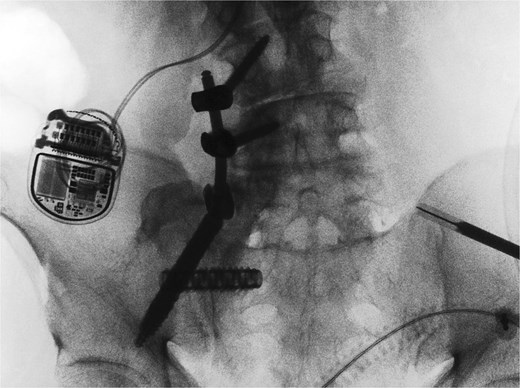

He was discharged home on postoperative day two, with instructions to remain toe-touch weight-bearing for three weeks. He was seen in the office two weeks after surgery. Lateral and antero-posterior pelvic radiographs showed good position of all hardware (Fig. 4). He reported mild incisional pain, but his preoperative pain had significantly improved. He was able to ambulate for the first time in years. Pain relief remains sustained three months after surgery.

Postoperative lateral (left) and AP (right) re-demonstrated good placement of the hardware.